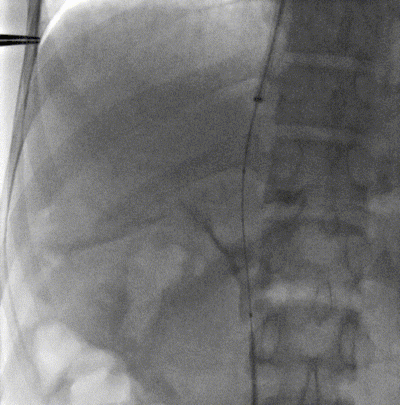

3. 经颈静脉置入10F导管鞘,下腔静脉置入大球囊在预定穿刺位置。

4. 经肠系膜静脉入路置入可调弯导管和空芯穿刺套件,调整方向后穿刺。

5. 穿刺成功后直接跟入泥鳅导丝至下腔静脉。

6. 经颈静脉置入抓捕器,引出泥鳅导丝,建立贯穿轨道。

7. 经肠系膜导管置入8mm球囊,扩张后将10F鞘管自下腔静脉引入门静脉远端。

8. 置入8*50mm覆膜支架建立门静脉下腔静脉分流道。造影提示:分流效果满意。